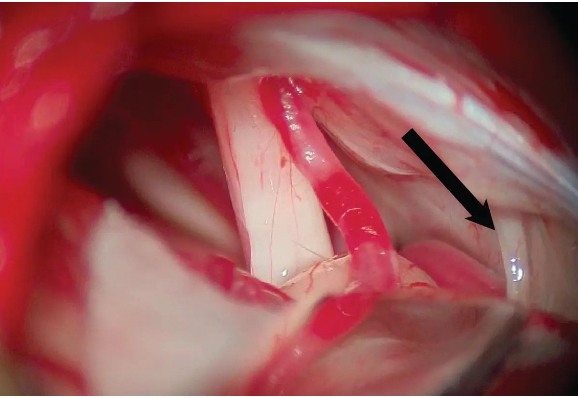

A patient presents with a one-year history of intermittent twitching of the right side of the face. During surgery to address the twitching, the nerve indicated by the arrow in the image shown is injured. This injury will most likely cause which of the following neurological deficits?

A. Unilateral Facial Numbness B. Vertigo

C. Dysphagia

D. Sensorineural hearing loss

E. Unilateral Facial Weakness

A

Correct Answer: Dysphagia